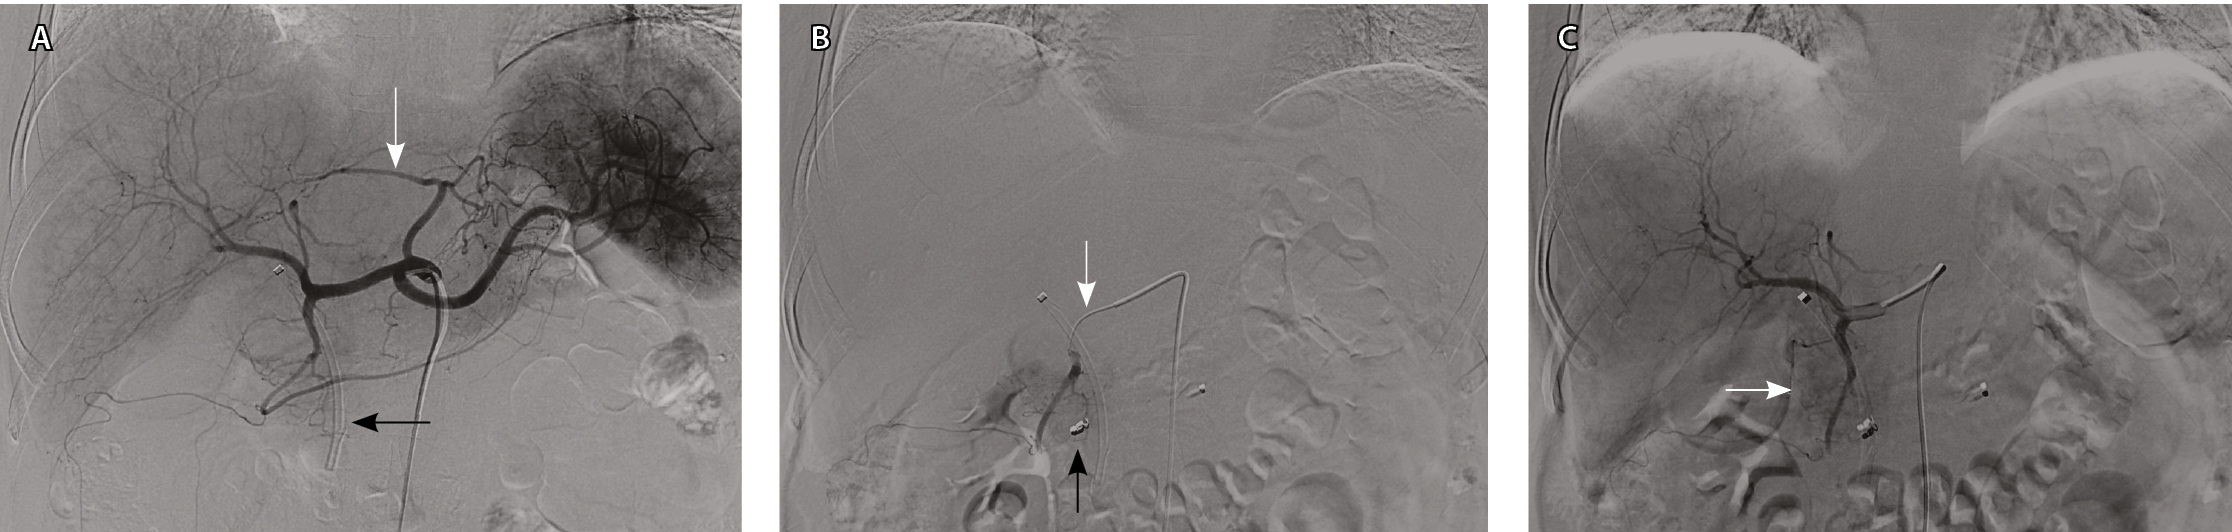

При проведении ангиографии использовали катетеры конфигурации hook или cobra (фирм Cook и Cordis, США или Terumo, Япония) размером 5 F. На ангиограммах из верхней брыжеечной артерии и чревного ствола определяли варианты сосудистой анатомии гепатопанкреатобилиарной зоны, источники кровоснабжения поджелудочной железы, состояние воротной вены по данным возвратной портографии. Затем осуществляли ангиографию общей, собственной печеночных и гастродуоденальной артерий (ГДА) для изучения ангиографических особенностей РПЖ, исключения или подтверждения метастатического поражения печени. Определяли оптимальное место установки катетера в положение, необходимое для проведения лечебного этапа процедуры (рис. 2).

Рис. 2. Ангиограммы пациентки Ш., 67 лет, диагноз: рак головки поджелудочной железы. Механическая желтуха купирована с помощью стентирования. А – при целиакографии отмечается один из вариантов сосудистой анатомии: замещающая левая печеночная артерия отходит от левой желудочной артерии (белая стрелка), правая и средняя – от общей печеночной артерии; пластиковый стент (черная стрелка) определяется в проекции холедоха. Б – катетер cobra 5 F установлен в общую печеночную артерию; коаксиально в правую желудочно-сальниковую артерию проведен микрокатетер 2,7 F, выполнена перераспределительная эмболизация металлической спиралью (черная стрелка); следующим этапом выполнена химиоэмболизация ветвей гастродуоденальной артерии, кровоснабжающих опухоль (белая стрелка). В – во время контрольной ангиографии из общей печеночной артерии отмечается накопление масляного препарата в опухоли (белая стрелка)

Для выполнения лечебного этапа катетер устанавливали в проксимальный отдел ГДА и медленно (для предупреждения рефлюкса по анастомозам) вводили химиоэмболизат, который готовили следующим образом: 300–600 мг/м2 гемцитабина растворяли в смеси 1:5 дистиллированной воды и 60% водорастворимого контрастного вещества (йопромид / йогексол / йоверсол). К раствору добавляли 2–4 мл сверхжидкого липиодола и добивались образования однородной суспензии ручным встряхиванием шприца в течение 3–5 минут. Процесс заполнения питающих сосудов опухоли химиоэмболизатом контролировали с помощью рентгеноскопии. После химиоэмболизации ГДА кончик катетера 5 F располагали в общей печеночной артерии или чревном стволе дистальнее левой желудочной артерии (для профилактики развития токсического гастрита или язвы). Пациента переводили в палату и проводили химиоинфузию: гемцитабин 1000 мг/м2 за 30 минут и сразу после этого оксалиплатин 75 мг/м2 за 120 минут (схема GEMOX).